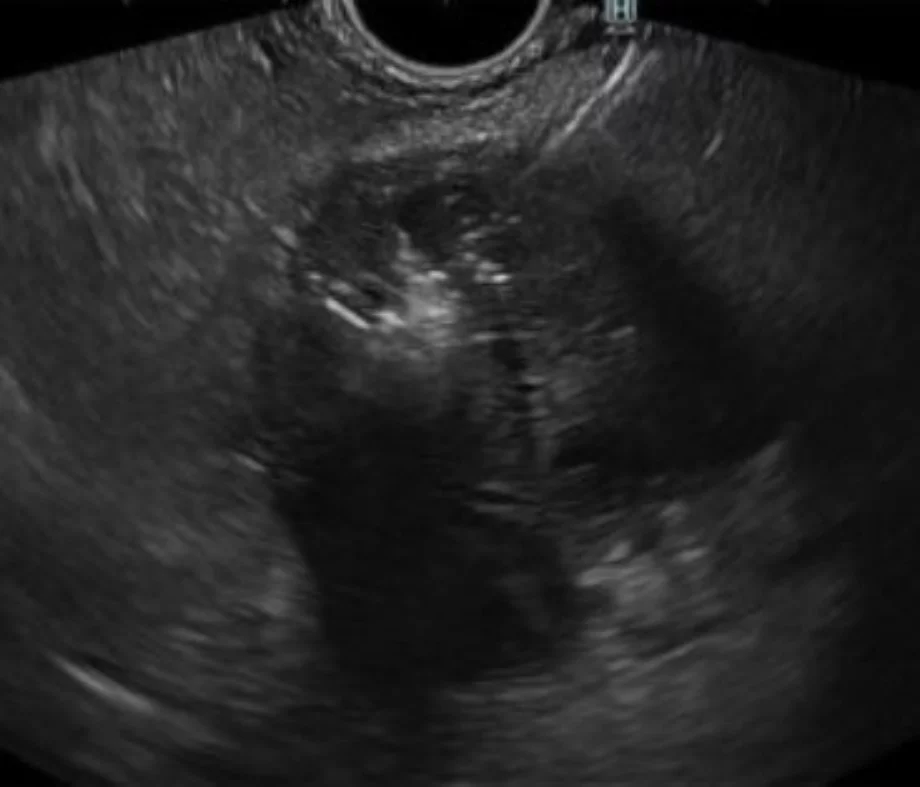

Novel EUS-guided microwave ablation of an unresectable pancreatic neuroendocrine tumor

Carlos Robles-Medranda, Martha Arevalo-Mora, Roberto Oleas, Juan Alcivar-Vasquez, Raquel Del Valle